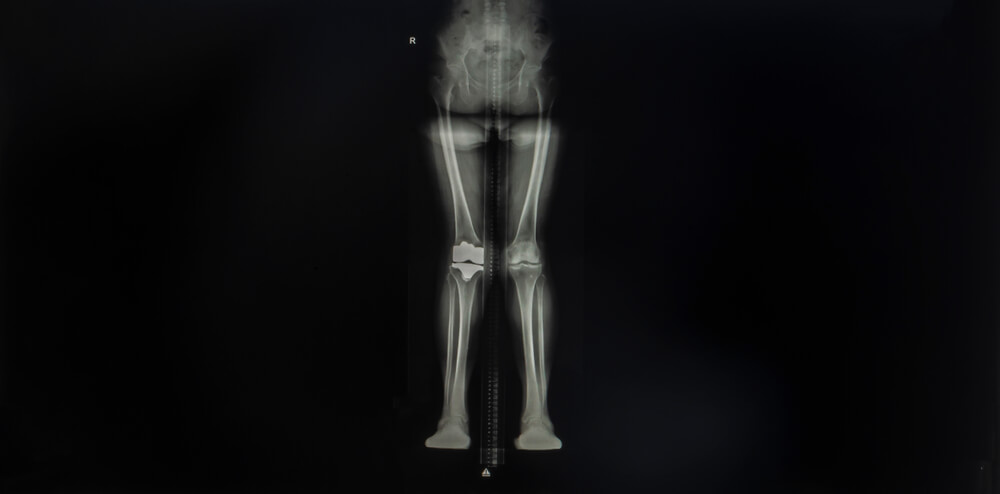

The viewing process is carried out by shooting both from the front and from behind. In this way, we ensure that clearer and more accurate results are obtained. In the case of scoliosis in the spine and lower back, we diagnose by shooting in this way. If there are any metal objects on the patient, they must be removed. Because metal items can cause the resulting images to be distorted and inaccurate. Metals also negatively affect the details of the image.

One of the reasons for the appearance of scliosis may be a genetic predisposition. You can find out if you have this problem by having a scoliosis film taken. At the same time, we use this imaging technique to detect the problem of leg shortness. You can get services from our health center to get rid of these problems that will reduce your quality of life and disturb you constantly. In this way, we will easily identify your existing problems and start treatment as soon as possible.

Scoliosis film, as the name implies, is mainly used to detect scoliosis disease. It is possible to encounter the problem of spinal curvature frequently in young children and people of developmental age. It may be possible to detect this condition within the scope of leg length measurement. If this disease is detected in a child of developmental age, treatment will be easier. There are many treatment methods that can be used in this case. Diseases can be easily detected with the advanced equipment used in our health center. The radiological examinations we perform using new generation devices help us to diagnose the problem of scoliosis. Then, the images we obtain are analyzed by our specialist physicians.

the radiation used in the Orthorontgenogram radiography technique is minimal. In this way, it will not harm the patient in any way. In other words, scoliosis radiography is a safe procedure. Shooting operations can be performed with or without measurement. The angle and degree of curvature are measured in the measurement scoliosis radiograph. Accordingly, appropriate treatment is determined. Scoliosis can develop in young children due to sitting. In this case, the thing to do is to try to eliminate it with simple treatments. The most appropriate treatment method is decided by the evaluation made by our specialist physicians.